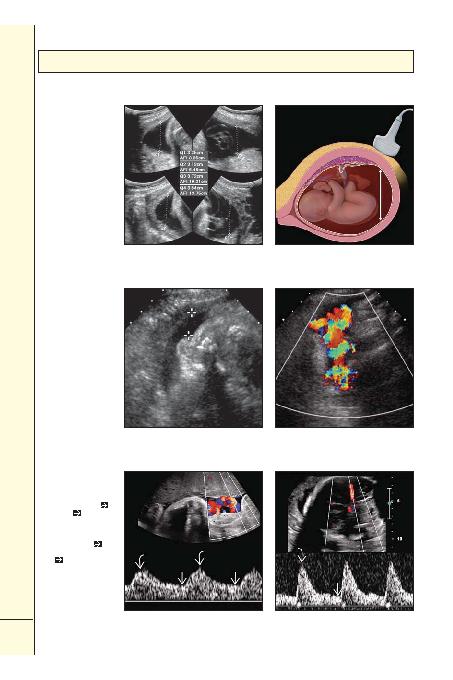

(Sol) ASæ hesaplamasÏ, 4 uterin

kadrandaki sÏvÏnÏn en geniã

cebindeki anterior-posterior

derinliçinin ölçülmesi (çizgiler)

ve bu 4 ölçümün toplanma-

sÏnÏ içerir.

(Saç) Diçer bir

objektif sÏvÏ ölçüm metodu ise

maksimum vertikal cep (MVC).

En geniã uterin sÏvÏ koleksi-

yonu bulunur ve maksimum

anterior-posterior mesafe

ölçülür.

(Sol) Oligohidramniyozlu

fetüsün transvers ultrasonog-

rafisi, baãlangÏçta küçük bir

sÏvÏ cebi olduçu düãünülen

alanÏ göstermektedir (iãaretler).

(Saç) Fakat, aynÏ alanÏn renkli

Doppler ultrasonografisi "sÏvÏ

cebinin" gerçekte umbilikal

kord olduçunu göstermektedir.

SÏvÏ ceplerinin ölçümünde

renkli Doppler kullanÏldÏ-

çÏnda amniyotik sÏvÏ volümü

deçerlendirmesi daha doçru

olacaktÏr.

(Sol) Normal umbilikal arter

dalga formu, kontinü diastolik

akÏma sahip düãük rezistif akÏma

sahiptir. Sistolik/diastolik oranÏ

(S/D), peak sistolik hÏzÏn

end

diastolik hÏza

bölünmesiyle

hesaplanÏr.

(Saç) Buna karãÏn,

burada aynÏ fetüsde görülen

normal orta serebral arter dalga

formu, sistolik akÏmla

karãÏ-

laãtÏrÏldÏçÏnda daha az diastolik

akÏma

sahip olan nispeten

yüksek rezistansa sahiptir.